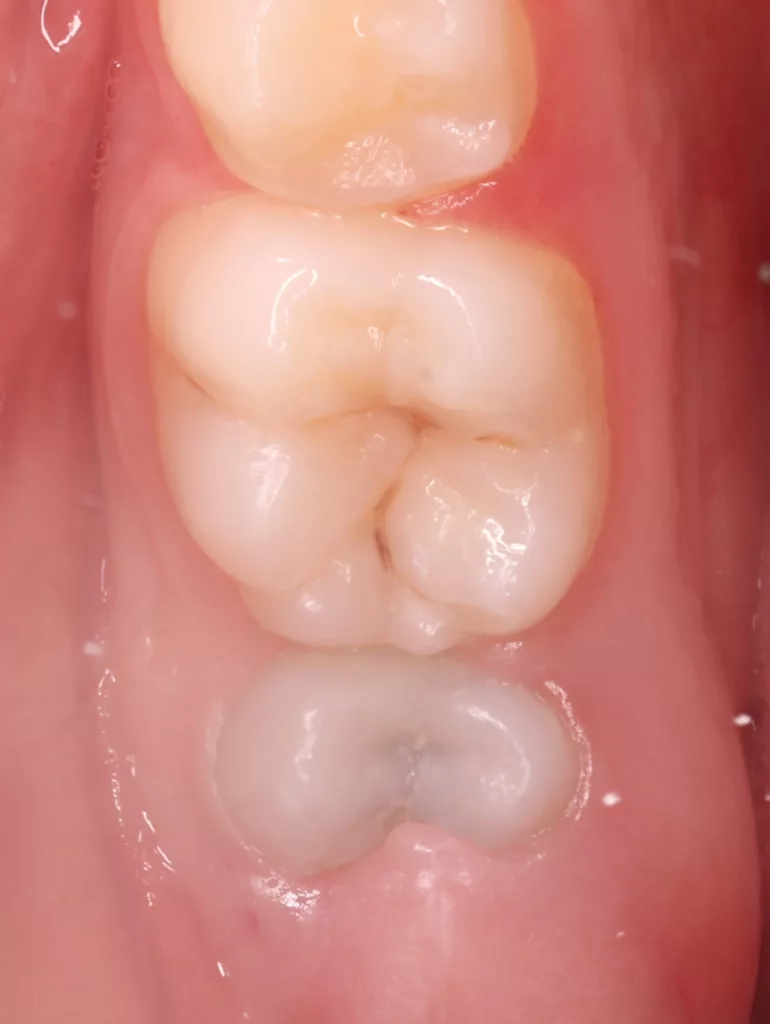

Bei routinemäßigen Röntgenkontrollen ergeben sich manchmal Zufallsbefunde unklarer Genese. So stellt sich beispielsweise bei der Betrachtung der Abbildung 1 die Frage, wie sich ein Zahnhartsubstanzdefekt so schnell entwickeln konnte. Ein weiteres Röntgenbild (Abb. 2), das vor dem Zahndurchbruch aufgenommen wurde, zeigt jedoch, dass es sich in diesem Fall nicht um Karies, sondern um die sogenannte präeruptive intrakoronale Resorption (PEIR) handelt. Für diesen Befund finden sich in der Fachliteratur auch noch andere Bezeichnungen wie „idiopathic external resorption of unerupted permanent teeth“ [1], „intra-follicular caries“ [2], „radiolucent lesions resembling caries“ [3], „occult caries“ [ 4] oder „pre-eruptive caries“ [5].

V. Slabkovskyi, O. Liutikovwährend des Durchbruchs des Zahnes 36.

Das fünfjährige Mädchen stellte sich 2017 zur jährlichen Routinekontrolle vor. Im Rahmen der Untersuchung wurden Röntgenaufnahmen der Milchmolaren gemacht (Abb. 2). Der klinische und radiologische Befund der vor uns früher gelegten Kompositfüllungen war gut, es wurde allerdings eine PEIR an den noch nicht durchgebrochenen ersten bleibenden Molaren festgestellt (Abb. 2). Den Eltern wurde empfohlen, sich unverzüglich bei Beginn des Durchbruchs der ersten Molaren erneut zur Behandlung vorzustellen. Ein Jahr später erschien die junge Patientin schmerzfrei zur Kontrolle. Der Zahn 36 war noch teilweise mit Gingiva bedeckt. Auf einer neuen Röntgenaufnahme (Abb. 1) wurde die PEIR-Läsion mit unveränderter Größe in pulpanahen Bereichen bestätigt (Grad 3 der Läsion nach Seow). Der Zahnschmelz sah intakt aus, es konnte kein pathologischer periapikaler Befund bei den noch nicht ausgewachsenen Zahnwurzeln festgestellt werden. Daraufhin wurden die verschiedenen Behandlungsmöglichkeiten von Fissurenversiegelung bis Vitalerhaltung der Zahnpulpa mit den Eltern des Kindes besprochen.